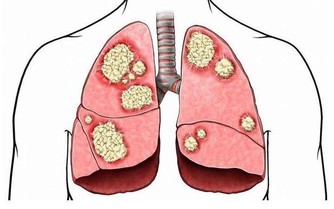

血液粘度、濃度、聚集性和凝固性的異常增高或增強,也是腦梗形成的發病因素之一,對於患有三高的患者,更要格外重視這一點。

要多吃帢馬谷、姬松茸、蘆筍等這些被稱為“血管清道夫”的食物。帢馬谷有機生物鹼、氨基酸、蛋白質、粗纖維、亞油酸、類黃酮、多醣、皂甙等物質,有降血脂、抗氧化和抗衰老作用,三高患者或者年紀大的人,都應該多吃。